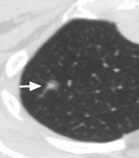

按照CT图像上结节密度的不同,结节分为实性结节和亚实性结节,而亚实性结节又分为部分实性结节和磨玻璃密度结节。实性结节是指看起来和人体软组织密度相似的病灶;磨玻璃密度结节是指肺内模糊的、半透明的结节影;而部分实性结节是指其内既有模糊的部分又有较高密度部分的病灶。在实性结节、部分实性结节和磨玻璃密度结节中,部分实性结节的恶性概率是最高的。

磨玻璃结节 部分实性结节 实性结节